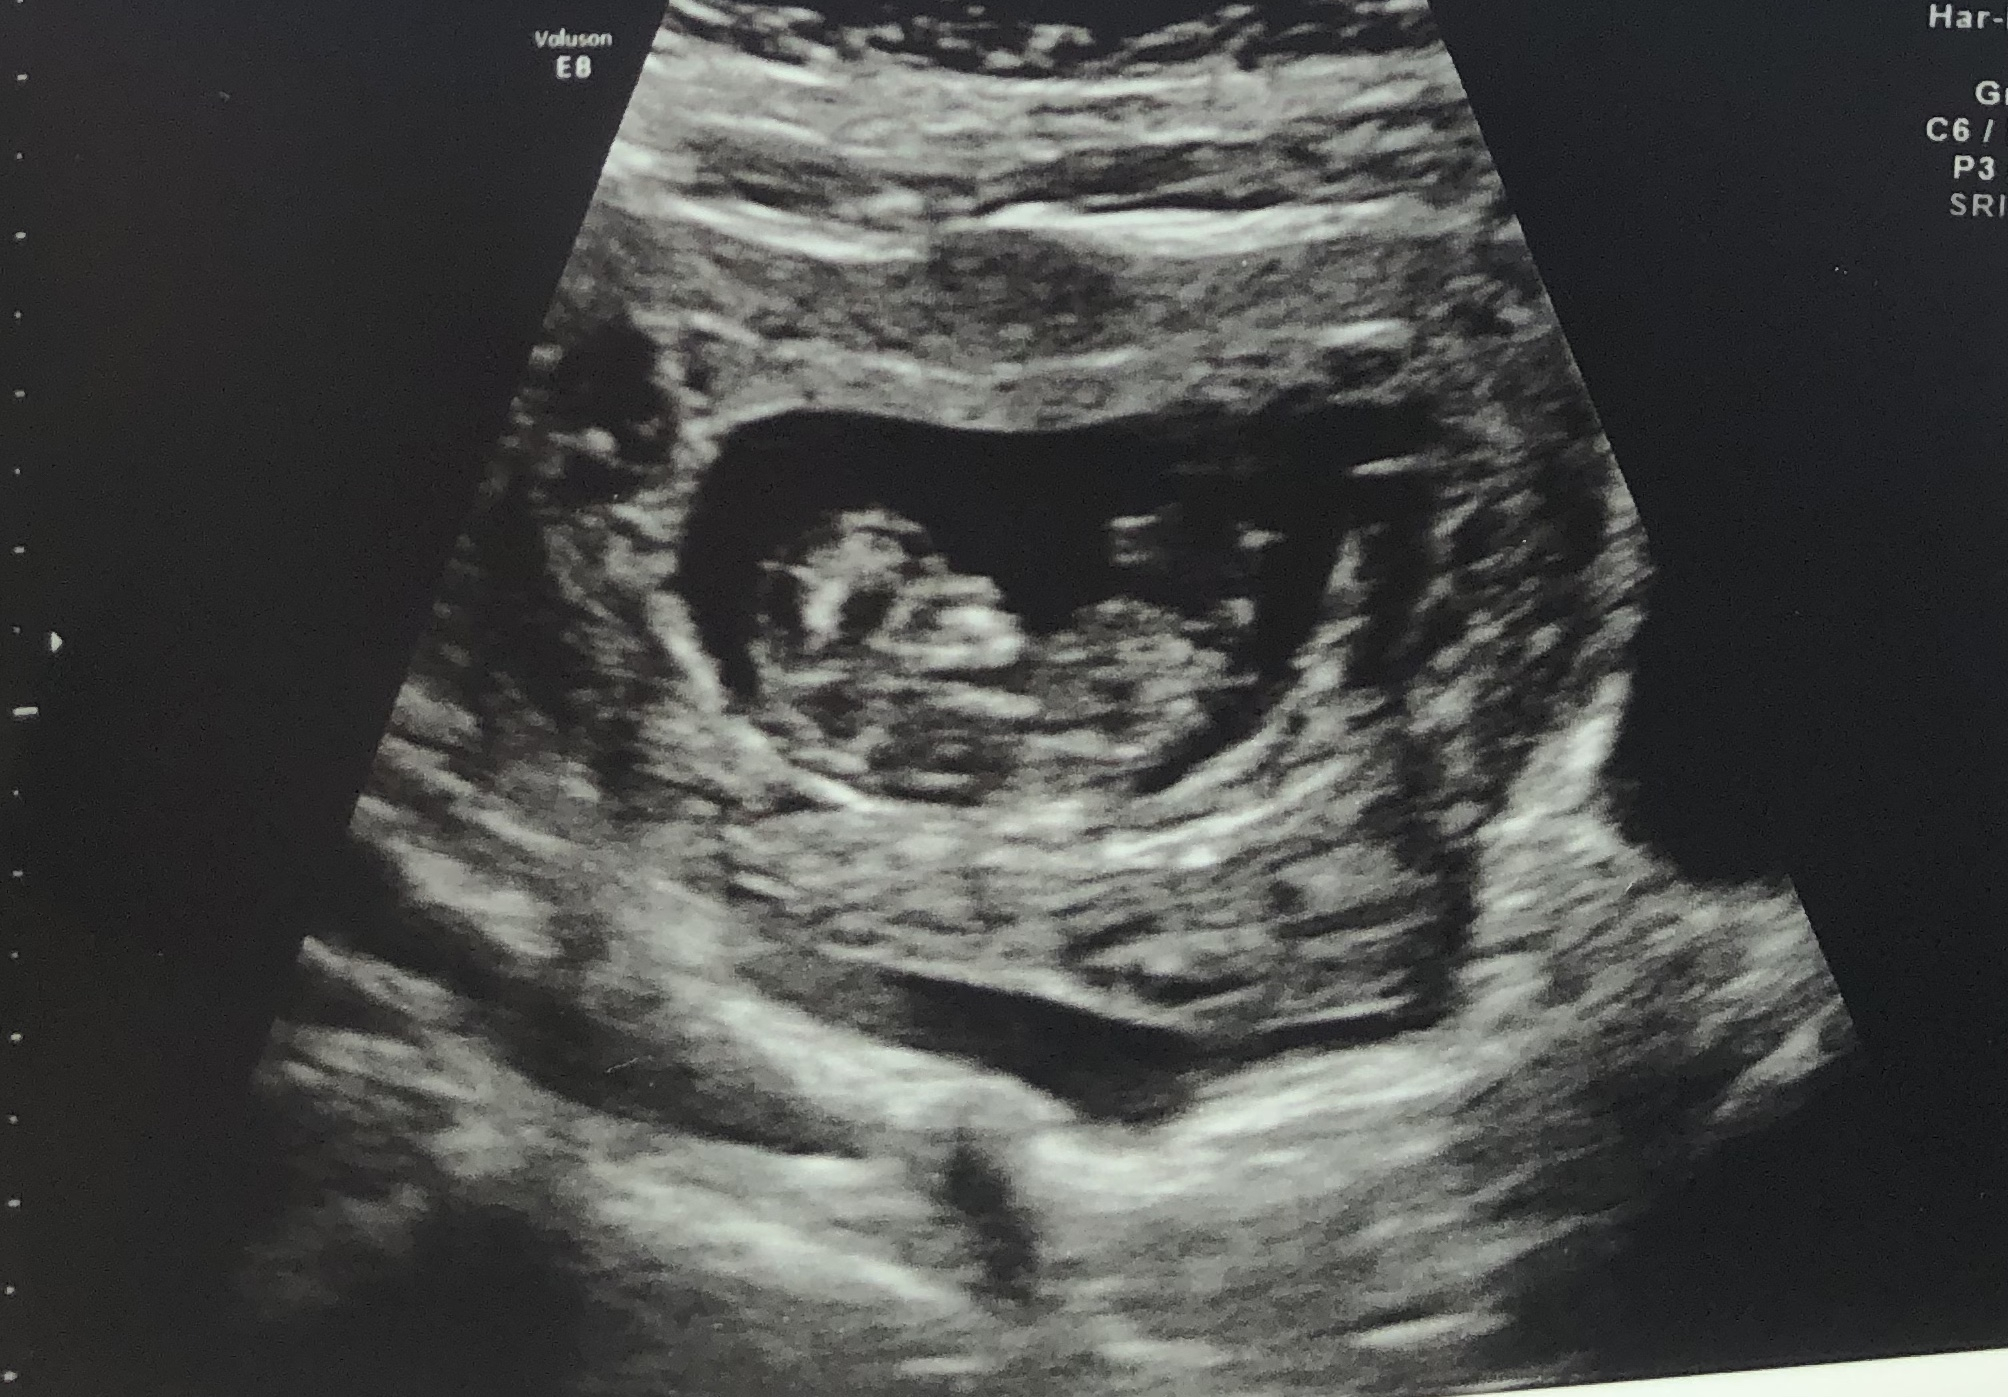

I had my 10w2d scan today and all 3 babies are doing great!! We can see arms and legs now. Baby 1 and 3 were wriggling up a storm during the scan. 2 babies were measuring 10w3d and 1 at 10w2d. HB between 160-180. I have another scan with the NT test in 2.5 weeks.